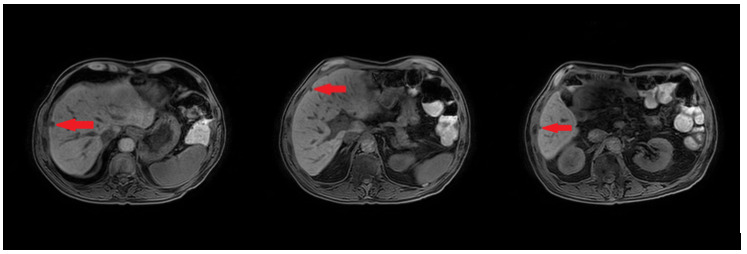

In February 2019, adjuvant chemotherapy with folinic acid, fluorouracil, irinotecan, and oxaliplatin (modified FOLFIRINOX) was initiated. About 2 months later, the serum laboratory test showed an increase in the level of the tumor marker, carbohydrate antigen (CA19.9) during chemotherapy (from 48.5 kU/l to 465 kU/l; normal range: <27.0 kU/L). In addition, a CT scan showed the appearance of 3 subcapsular lesions suspected to be metastases in the liver segment II and between liver segments V and VI (Figure 3). Thereafter, the patient received first-line palliative chemotherapy with nab-paclitaxel plus gemcitabine. A restaging with an abdominal MRI scan after 6 courses of chemotherapy showed a partial response manifested as a decrease in the size of the liver metastasis. No new lesions were detected. Furthermore, there was a progressive decrease of the CA19.9 level (from 465 kU/l to 55.2 kU/l) (Figure 4). Taking into consideration that the long-term survival of patients with AAC is usually improved as compared with PDAC patients and that radical surgery has been associated with favorable long-term survival, along with the patient’s motivation, we discussed the case in a multidisciplinary tumor board and decided for surgery of the liver metastasis.